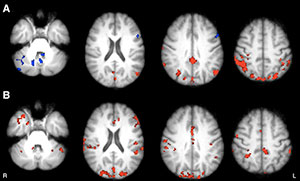

Axial statistical maps show areas of reduced thalamic functional connectivity (FC) in patients with MS compared with that in healthy subjects.

Figure 1: Axial statistical maps show areas of reduced thalamic functional connectivity (FC) in patients with MS compared with that in healthy subjects. Patients exhibited significantly lower FC in clusters located in the cerebellum, frontal and occipital cortices, caudate nucleus, and thalamus, bilaterally.

Axial functional connectivity (FC) maps show changes in thalamic FC after 8 weeks in both groups of patients with MS. Areas of increased FC are represented in red, areas of reduced FC in blue.

Figure 3: Axial functional connectivity (FC) maps show changes in thalamic FC after 8 weeks in both groups of patients with MS. Areas of increased FC are represented in red, areas of reduced FC in blue. A, Intervention group shows increased FC in occipital, medial, and lateral parietal and posterior cingulate cortices, bilaterally; decreased FC in vermis and left dorsal-lateral prefrontal cortex. B, Wait-list group shows increased FC in frontal, occipital, and medial parietal cortices, bilaterally; cerebellum; and right temporal lobe.